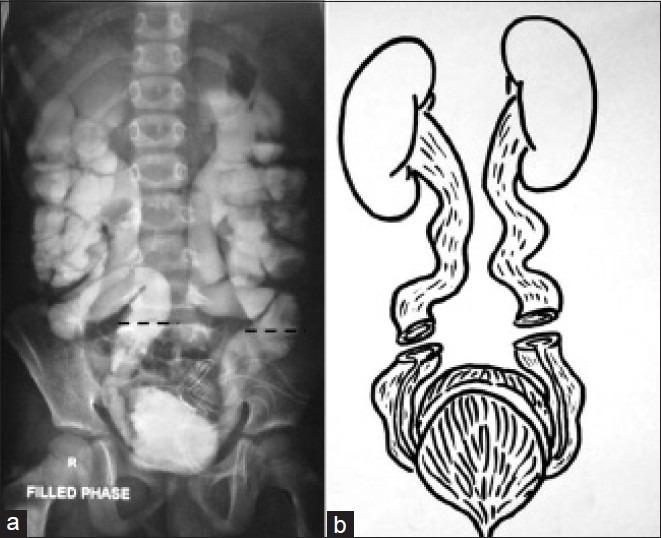

A novel technique of bladder augmentation is reported, wherein the distal dilated ends of tortuous ureters were used for ureterocystoplasty while proximal remaining ureters reimplanted back into the native bladder.

报道了一种新型膀胱扩大术,其中将迂曲输尿管的远端扩张端用于输尿管膀胱成形术,而将近端剩余输尿管重新植入原生膀胱。